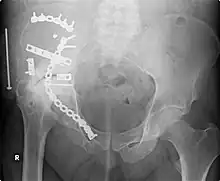

X-ray of a hip replacement

The modern total hip replacement was pioneered by Sir John Charnley, expert in tribology at Wrightington Hospital, in England in the 1960s.[10] He found that joint surfaces could be replaced by implants cemented to the bone. His design consisted of a stainless steel, one-piece femoral stem and head, and a polyethylene acetabular component, both of which were fixed to the bone using PMMA (acrylic) bone cement. For over two decades, the Charnley low-friction arthroplasty and its derivative designs were the most-used systems in the world. This formed the basis for all modern hip implants.

This image, taken in September 2006, shows extensive repair work to the right acetabulum six years after it was carried out (2000). The onset of arthritis, a bone/joint disease, has made further joint damage visible.